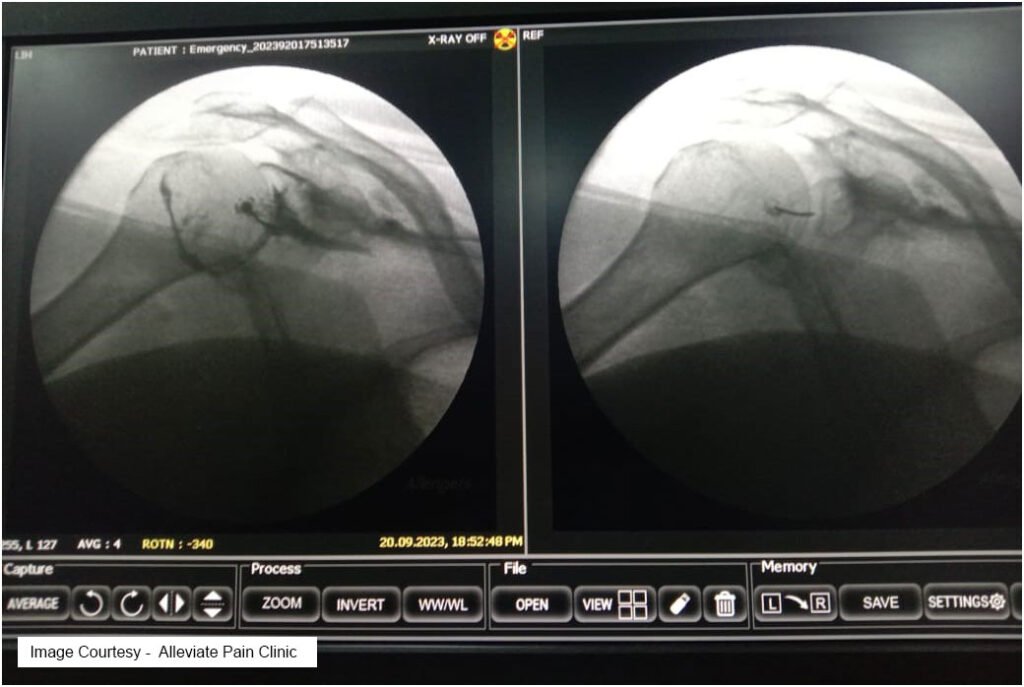

Hydrodilatation (Distension Arthrogram)

- Procedure : Hydrodilatation is a minimally invasive procedure that entails the injection of a sterile fluid (typically saline) into the joint capsule, stretching it and breaking up adhesions.

- Mechanism : The injected fluid distends the capsule, physically separating adhesions and promoting the release of fibrotic tissue. This procedure also helps to restore joint lubrication and improve range of motion.